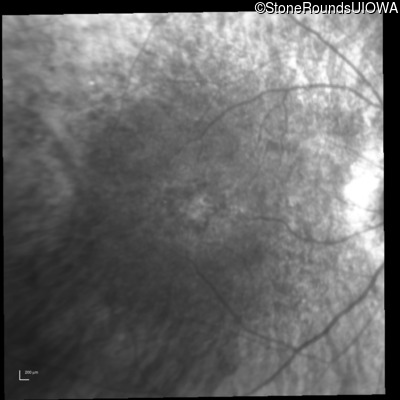

Infrared Fundus Photograph - Right - 20/80 +1

Exemplar